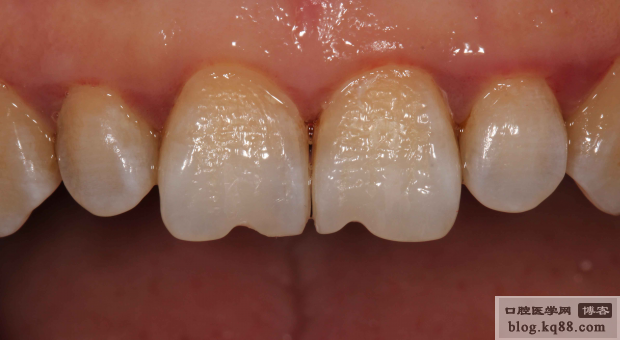

術(shù)后唇側(cè)